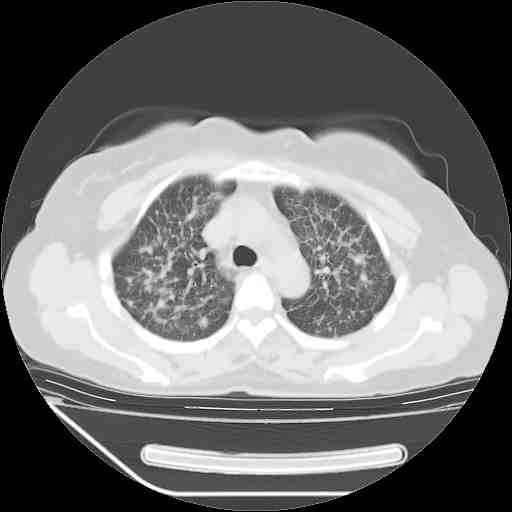

f50,肺ca治疗后,做过穿刺,确诊是肺ca,大家看看这是去年12月做的

下面是今天刚刚做的,在上海治疗,吃了家属也说不清的一种药,一个月1万左右,